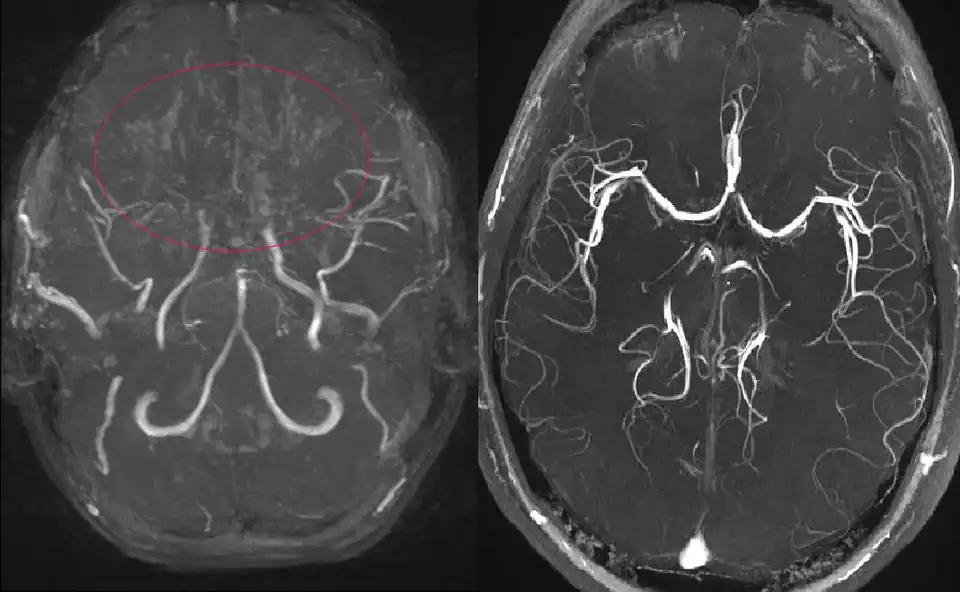

Ressonancia magnética de uma menina de 11 anos com Moyamoya

A angiografia por ressonância magnética (RM) e a angiografia por tomografia computorizada são métodos de diagnóstico não invasivos. As imagens de RM de alta resolução da parede do vaso também ajudam a diagnosticar a DMM, revelando um estreitamento concêntrico da parede do vaso com colaterais basais. A doença de Moyamoya (DMM), significa uma "nuvem de fumo" em japonês, também designada por oclusão espontânea do círculo de Willis, é uma doença cerebrovascular oclusiva crónica de etiologia desconhecida, caracterizada por alterações estenooclusivas na porção terminal da artéria carótida interna (ACI) e por uma rede vascular anormal na base do cérebro.[1] Tendo em conta o número crescente de doentes com envolvimento unilateral,[2] bem como a evidência de que um número substancial de casos unilaterais progride para uma apresentação bilateral,[3][4] os critérios de diagnóstico para a DMM definitiva foram revistos de modo a incluir doentes com apresentação bilateral e unilateral de estenose da ACI terminal com uma rede vascular anormal na base do cérebro (declaração do Comité de Investigação da DMM do Ministério da Saúde, Trabalho e Bem-Estar do Japão em 2015). Os critérios de diagnóstico também indicam que o diagnóstico definitivo da DMM requer uma angiografia por cateter nos casos unilaterais, ao passo que os casos bilaterais podem ser prontamente diagnosticados quer por angiografia por cateter quer por ressonância magnética/angiografia (RM/ARM). Quando há doenças causadoras ou condições associadas, termos como síndrome de moyamoya e moyamoya angiográfica são freqüentemente usados.[5] Embora incomum, a DMM é uma importante causa de doença arterial intracraniana não aterosclerótica, especialmente nos países do leste asiático. Nessas regiões, a estenose isolada da artéria cerebral média é observada em pacientes jovens, com eventual evolução para DMM.[6] A DMM é a causa mais importante de AVC ou ataque isquémico transitório (AIT) em crianças nesta parte do mundo.

A ressonância magnética e a angiografia por RM podem demonstrar pequenas lesões subcorticais que são frequentemente indetectáveis na TC. A ressonância magnética e a angiografia provaram ser úteis porque a DMM envolve frequentemente enfartes pequenos e múltiplos. Essas modalidades de imagem permitem a visualização das porções distais ocluídas da ACI. Os vasos de Moyamoya aparecem como vasos finos incomuns na angiografia por RM ou como um vazio de sinal na imagem por RM. No entanto, tanto a imagem por RM como a angiografia por RM visualizam mal os vasos de moyamoya mais pequenos. A ressonância magnética pode ser usada como substituta da angiografia convencional em crianças, de acordo com os critérios diagnósticos da DMM (Tabelas 1 e 2), se a oclusão for claramente observada bilateralmente.[91][82][92] A angiografia por ressonância magnética pode detectar algumas lesões não observadas na RM, mas muitas vezes superestima a extensão da lesão. O aumento do sinal obtido com magnetos 3-T mais potentes fornece detalhes angiográficos significativamente maiores.[93] Além disso, a angiografia por RM pode ser usada no pós-operatório para determinar o estado do fluxo colateral e a patência dos enxertos de bypass extracraniano e intracraniano. A angiografia por ressonância magnética é limitada na resolução espacial e na avaliação da direcção do fluxo; embora esta última possa ser avaliada na angiografia por RM resolvida no tempo, esta técnica continua a sofrer de uma resolução espacial muito fraca.[94] Em termos gerais, a imagiologia por RM e a angiografia por RM são bons métodos para detectar a DMM, especialmente quando esta se encontra na fase 3 ou 4, mas não são muito eficazes como meio de estadiamento da doença.[95]